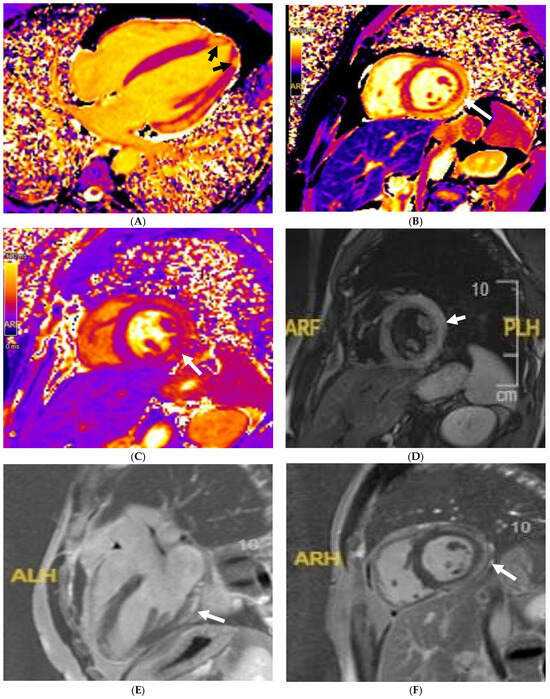

Tissue characterisation with cardiac MRI also plays a key role in athletes with a suspicion of HCM. Post-contrast imaging with late-gadolinium enhancement (LGE) is used to detect macroscopic replacement fibrosis (Figure 3). The presence of fibrosis is diagnostic of a disease process, often patchy and present in hypertrophied segments. Extensive LGE has also been associated with an increased risk of ventricular arrhythmias and SCD [67,68,69]. LGE is, however, only present in 60% of HCM cases [68,70], implying that the absence of fibrosis should not preclude labelling an athlete with HCM. T1 mapping has an important role in LGE-negative HCM cases. Myocyte hypertrophy, rather than expansion of the extracellular matrix, often leads to lower T1 values, especially in endurance and male athletes. This provides a valuable insight into the pathophysiological process of athletes with LV hypertrophy [71,72,73]. Pathological LVH, on the other hand, is positively correlated with ECV, suggesting that an increase in the extracellular matrix is the main contributing factor towards an elevated LV mass [74]. T1 mapping certainly holds promise, yet it requires extensive validation in large athletic cohorts with HCM. LGE and mapping sequences may also play a diagnostic role in HCM phenocopies when cardiomyopathy coincides with extracardiac manifestations. There is a typical abnormal post-contrast myocardial nulling in cardiac amyloidosis. T1 values are, conversely, significantly reduced in Fabry’s disease [75].

Figure 3. Caucasian male soccer player presenting with inferolateral T-wave inversion on ECG. SSFP cine imaging (A) showing apical hypertrophy, with evidence of apical fibrosis on post-contrast imaging (B,C).

Small-vessel disease and microvascular dysfunction is a phenotypic trait in some HCM patients, often leading to a demand and supply perfusion mismatch in HCM patients (Figure 4) [58,76]. One small study also confirmed that coronary vasodilation reserve is preserved in athletes with physiological LV hypertrophy but reduced in patients with HCM [77], suggesting it may play a role when evaluating athletes in the grey zone. Data supporting routine ischaemia testing in athletes with HCM are inexistent. For HCM athletes who report chest pain without a documented LVOT obstruction (either at rest or during exercise) and epicardial coronary disease, our current practice is to perform perfusion imaging to specifically rule out microvascular dysfunction.

Figure 4. A 21 year old male that presented with chest pain during a pre-participation evaluation to join the armed forces. ECG showing biphasic ST segments in leads V1-V3, with T-wave inversion in II/III/aVF. CT coronary angiogram ruled out epicardial coronary disease. A stress echocardiogram ruled out dynamic LVOT obstruction. Echocardiogram confirmed the presence of hypertrophic cardiomyopathy, secondary to a likely pathogenic MYBPC3 variant. Cardiac MRI (3T scanner) showing septal hypertrophy (arrow) (A), extensive replacement (arrow) (B), and interstitial fibrosis in the septal segments (arrow) (C) (T1 map using a MOLLI 5b(3b)3b [3T]). Perfusion imaging (D) also identifying an extensive perfusion defect (arrow) in the hypertrophied segments, confirming microvascular dysfunction.